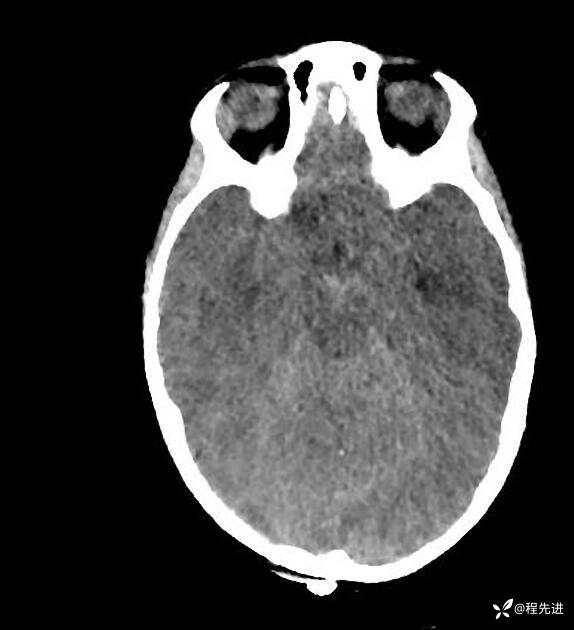

患者性别:男

患者年龄:5岁

简要病史:超速车祸外伤半小时

急诊CT平扫: